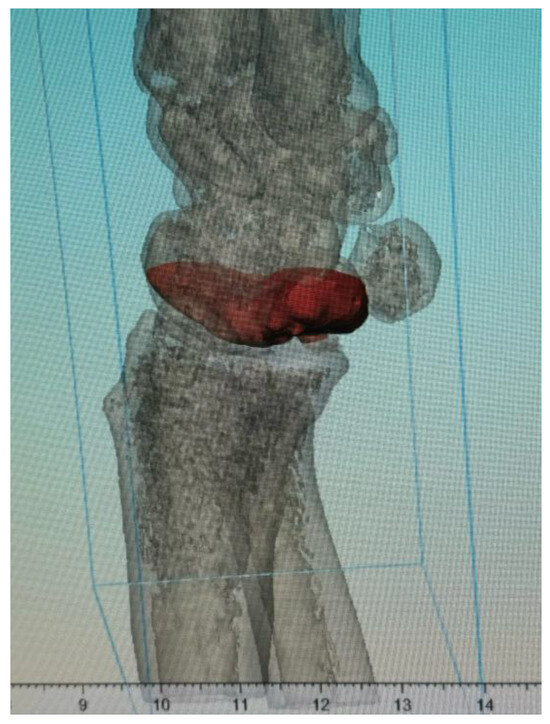

3.1. Clinical Case

3.1.1. Case 1

3.1.2. Case 2